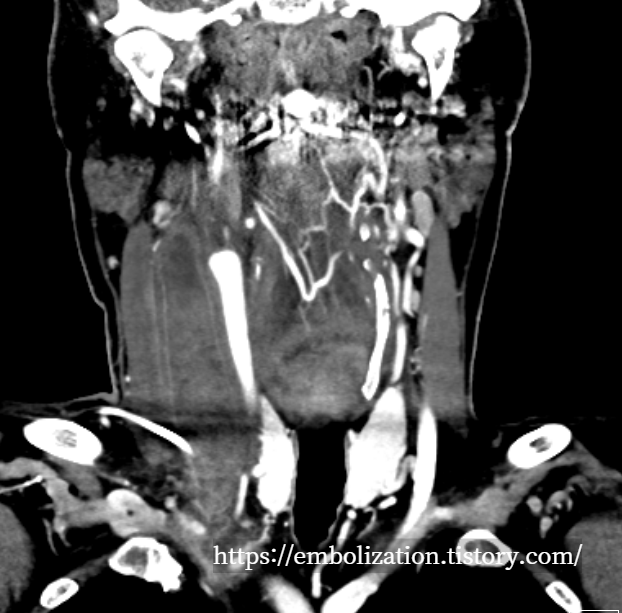

Acute thrombophlebitis in right IJV

Chief complaint : Neck pain